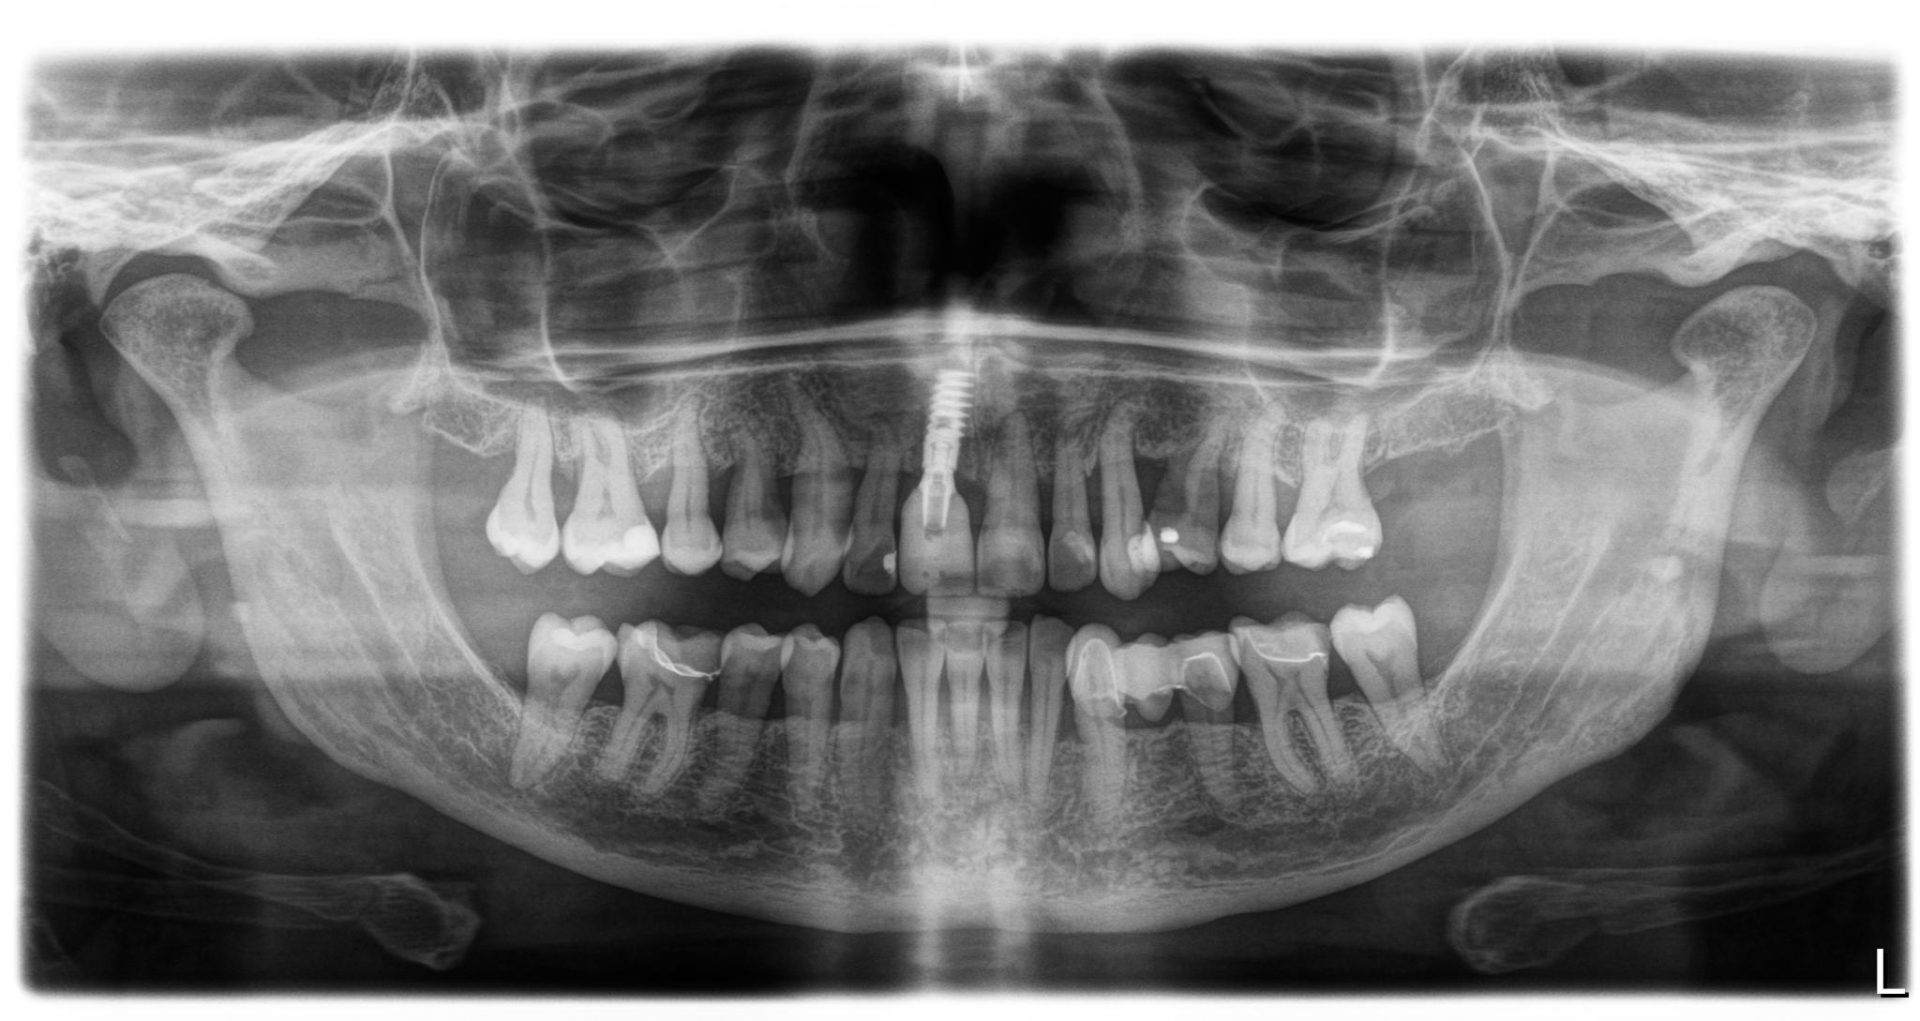

Parodontie Sévère

Grosse perte osseuse visible sur

la radio   on pourrait avec un stylet marquer en 2 couleurs le niveau osseux

actuel et normal

avant traitement